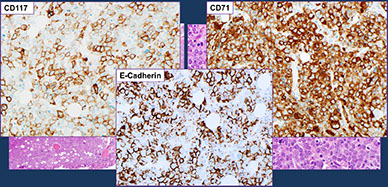

Characteristic morphologic findings in the myeloid/lymphoid neoplasm with PCM1-JAK2 rearrangement. A-C, Typical bone marrow histopathology features of PCM1-JAK2–rearranged chronic myeloid neoplasm (case 247) showing hypercellularity, large aggregates/nodules of immature erythroblasts (larger area outlined in A and demonstrated by E-cadherin [C]), eosinophilic infiltrate (B, from the smaller area outlined in A), and frequent fibrosis. [6]

Extramedullary involvement is very common in PCM1-JAK2–rearranged neoplasms, often with aggregates of immature erythroblasts and eosinophilia mirroring bone marrow features. Case 255 shows a lymph node with architectural effacement by large sheets of immature

erythroblasts (D and F), as highlighted by CD71 (E and G), consistent with myeloid sarcoma, erythroblastic type. [6]